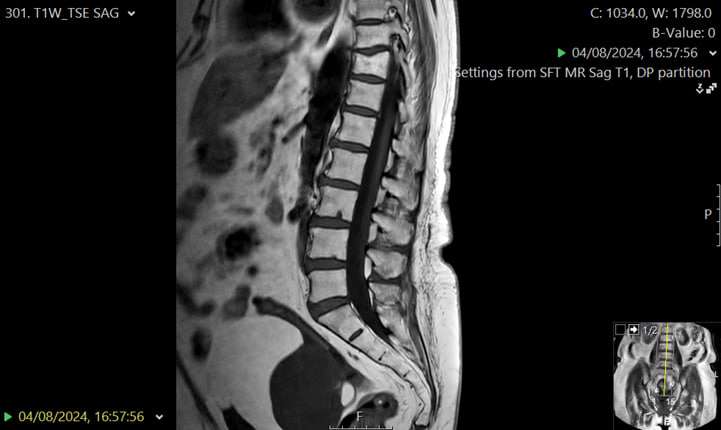

- Lumbar spine MRI scan – to evaluate for nerve root compression or spinal stenosis causing referred pain

An urgent MRI scan of the lumbar spine demonstrated a large pelvic mass arising from the adnexal region, causing compression of the lumbosacral plexus. This explained the patient’s severe bilateral hip and thigh pain, which clinically mimicked meralgia paraesthetica.

The patient was referred urgently to the gynaecology team, where further evaluation confirmed a low-grade ovarian tumour. The lesion was surgically excised, and the patient remains under ongoing gynaecological follow-up.

- Consider advanced imaging (e.g. MRI of the pelvis and lumbar spine) when initial investigations are inconclusive.